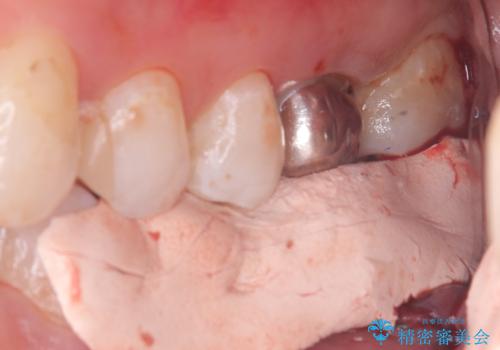

保存が難しい左下6番目の歯を抜歯し、左下8番目の歯(親知らず)を抜歯窩に移植しました。歯牙移植後の動揺防止のため暫間固定を行っています。

また移植後2週間経過時点で根管処置が必要となります。

骨との定着を確認し、今後矯正治療を行う予定のためレジン冠をセットしています。